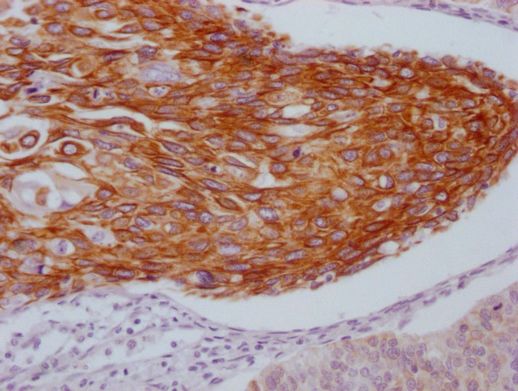

• IHC image of CSB-MA550667 diluted at 1:100 and staining in paraffin-embedded human cervical cancer performed on a Leica BondTM system. After dewaxing and hydration, antigen retrieval was mediated by high pressure in a citrate buffer (pH 6.0). Section was blocked with 10% normal goat serum 30min at RT. Then primary antibody (1% BSA) was incubated at 4°C overnight. The primary is detected by a Goat anti-mouse IgG polymer labeled by HRP and visualized using 0.05% DAB.